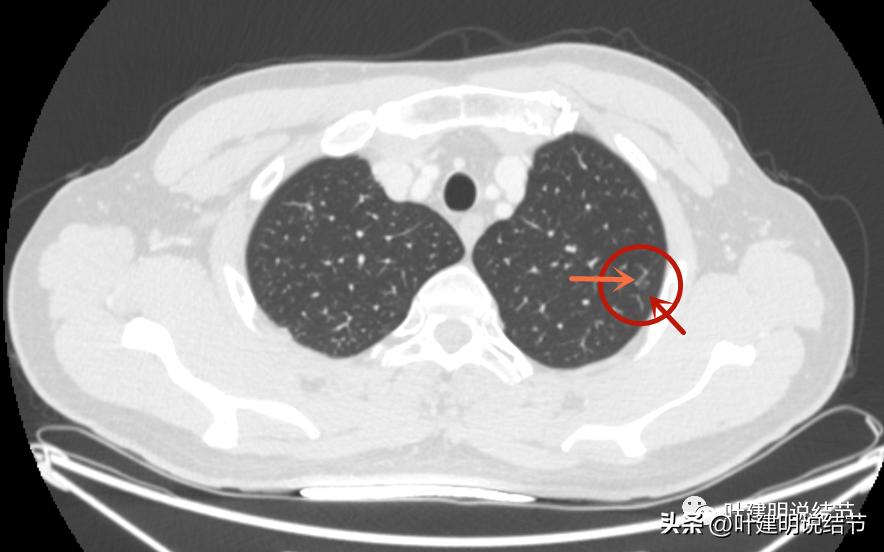

病灶2:右上叶结节

右上有微小磨玻璃结节,见血管穿行,整体密度也不高,但似乎比左侧的略高点。

病灶轮廓较清。

这两处结节均考虑是肿瘤范畴的,因为轮廓清,磨玻璃密度,并有血管穿行。但整体均还上,密度还很低,尤其左侧的密度更低。这样密度极低的磨玻璃结节,它周围的血管贴边并不似因为肿瘤生长需要富血供,从而吸引了新生血管过来,或周围血管发出分支来供血,而是“碰巧”有血管刚好经过的可能性更大些,且淡磨玻璃密度的结节基本不具有侵袭性,不至于侵犯或影响血管从而带来危险。如果一定要来预估一下病理会是什么,大概左侧以不典型增生可能性大,不能除外原位癌;右侧稍倾向原位癌,但也可能是不典型增生或肺泡上皮增生,至少近期风险低,能随访。

左侧磨玻璃结节红色圈起来的瘤肺边界清,有血管贴边,但整体密度低,没有实性成分,考虑仍是不典型增生或原位癌阶段,近期风险低,个人觉得最好先随访,因为可能很多年不变的,而且也可能再检出新的结节来。况且随访有进展再干预,效果也是一样的。右侧结节也是肿瘤范畴,但风险一样不高,建议同样半年到一年复查(其实1年也关系不大的)。意见供参考!